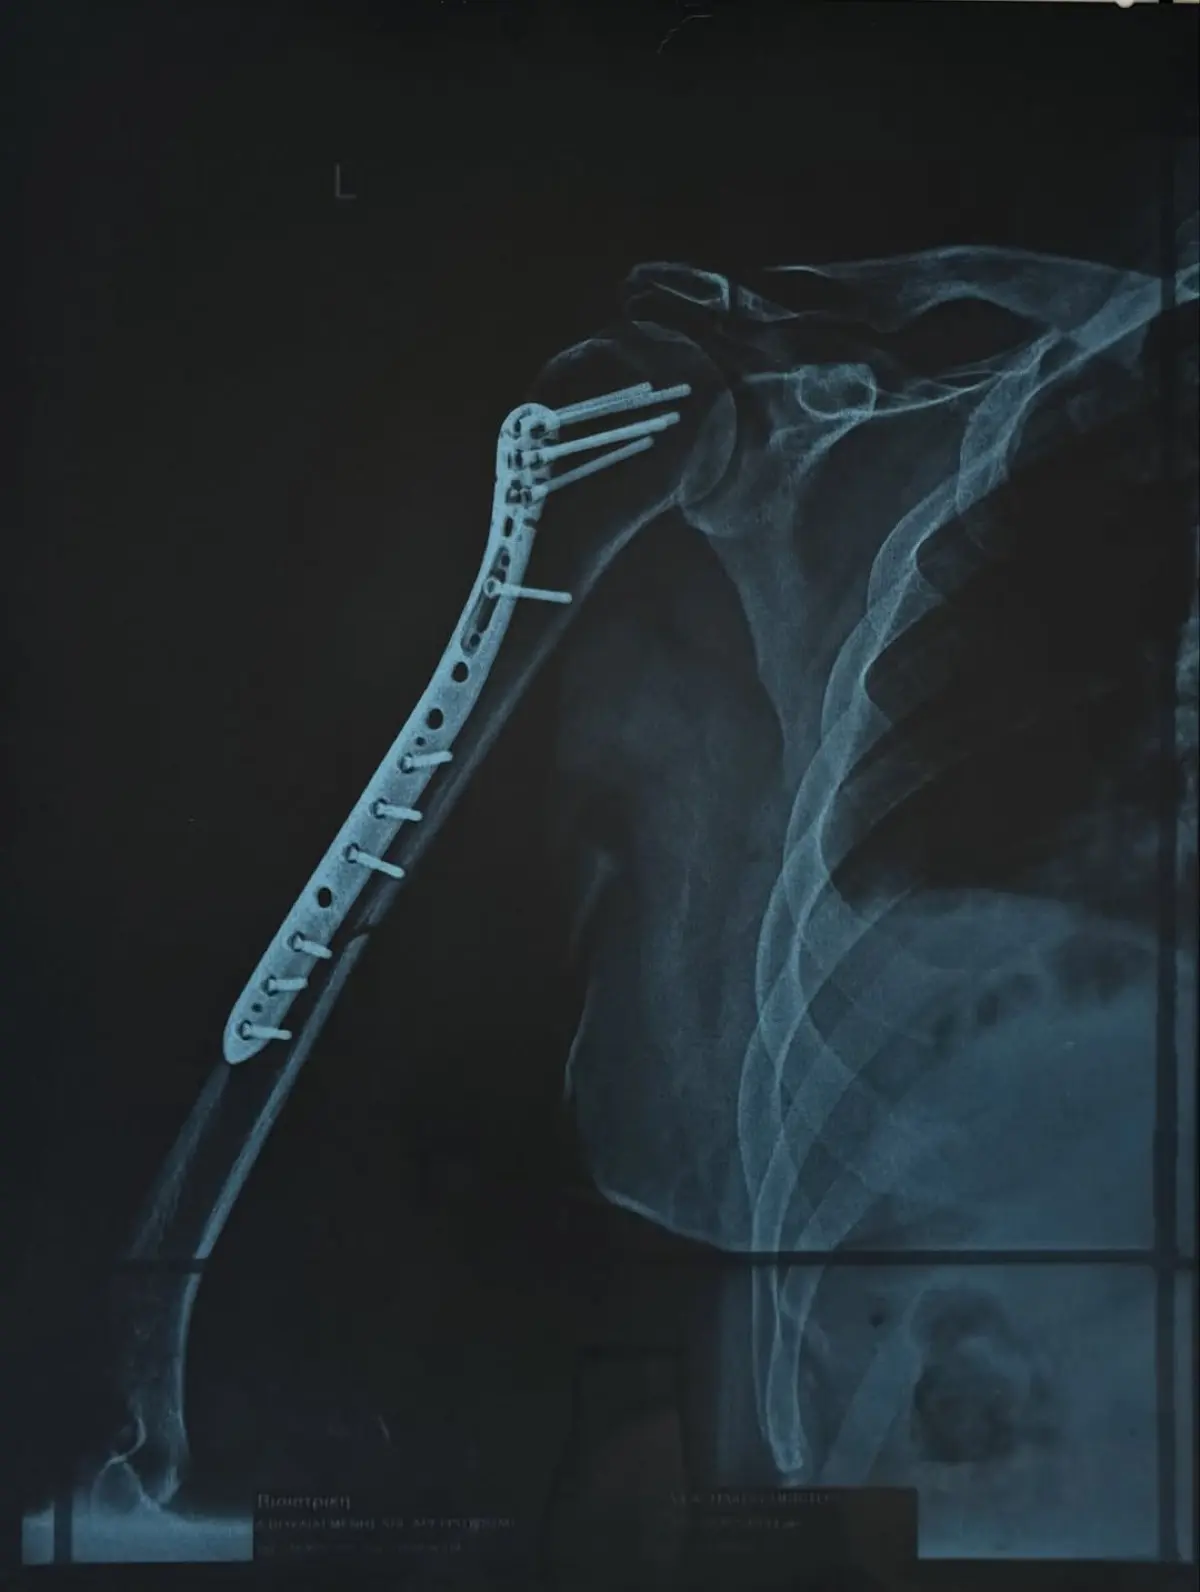

Δύσκολες ώρες πέρασε ο Χρήστος Δάντης, καθώς υπέστη κάταγμα στο χέρι και χρειάστηκε να υποβληθεί σε χειρουργική επέμβαση. Ο γνωστός τραγουδιστής και συνθέτης μεταφέρθηκε στην Ευρωκλινική Αθηνών το βράδυ της Πέμπτης, με την κατάσταση του χεριού του να είναι ιδιαίτερα επιβαρυμένη, όπως περιέγραψε ο ίδιος.

Μέσα από ανάρτησή του, ο τραγουδιστής θέλησε να ευχαριστήσει δημόσια τον γιατρό που τον χειρούργησε, περιγράφοντας τη δύσκολη κατάσταση στην οποία βρέθηκε πριν μπει στο χειρουργείο.

«Όταν θυμάμαι σε ποια κατάσταση μπήκα στην Ευρωκλινική Αθηνών το βράδυ της Πέμπτης, με το χέρι σχεδόν διαλυμένο και σκέφτομαι πόσο γρήγορα θα ανέβω ξανά στη σκηνή την Παρασκευή που έρχεται… μόνο ευγνωμοσύνη μπορώ να νιώσω.

Το «τεράστιο ευχαριστώ» ανήκει στον Χειρουργό Γιώργο Μάζη @shoulderexpert και σε όλο το επιτελείο του, αν και είναι λίγο μπροστά σε αυτό που έκαναν για μένα. Με χειρούργησαν και μου «έδωσαν» πίσω το χέρι μου και τη δυνατότητα να επιστρέψω εκεί που ανήκω: στη σκηνή!», έγραψε στην ανάρτησή του ο Χρήστος Δάντης.